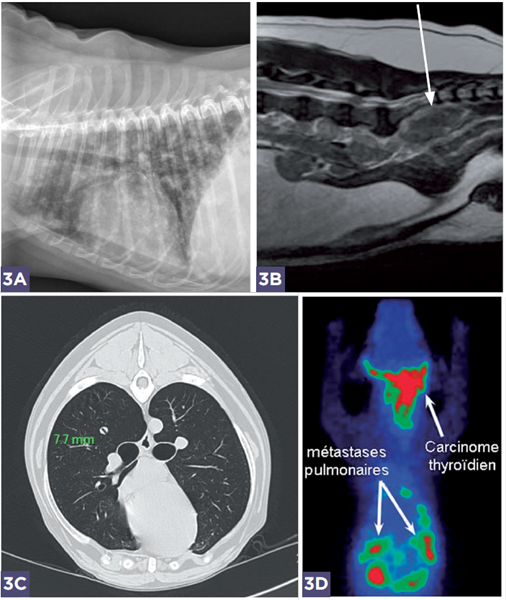

Photos 3A-B-C-D

En fonction du type de la tumeur, un bilan d’extension est systématiquement réalisé. En général, les sarcomes ont plutôt tendance à métastaser dans les poumons et les carcinomes envahissent d’abord les noeuds lymphatiques.

Le bilan d’extension peut être commencé avec la radiographie ou l’échographie mais reste plus précis avec de l’imagerie en coupe (scanner, IRM) ou la scintigraphie.

3A : métastases pulmonaires sur des tumeurs mammaires.

3B : nœuds lymphatiques sous-lombaires envahis par des métastases de carcinome des glandes anales à l’IRM.

3C : nodule pulmonaire de 7 mm avec un ostéosarcome au scanner.

3D : scintigraphie dans le cas d’une tumeur thyroïdienne.